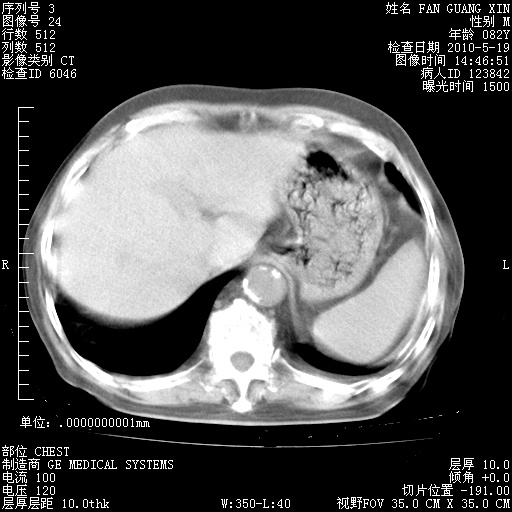

再治疗10天后的肺部CT 纵膈窗

阅读此次胸部CT,肺间质渗出性改变较入院时有吸收。目前从体温、白细胞、中性分叶明显增高,肯定存在细菌感染(发生医院感染哦,若无消化道及泌尿系统等感染的依据,肺部感染可能大)。若你院头孢哌酮舒巴坦钠耐药率较高,同意你的方案,若48小时体温仍高,可考虑使用碳青霉稀类抗菌药物,同时可予超声雾化、注意滴数时加大液体量。白蛋白33.30g/L较低哦,需加强营养等支持治疗。